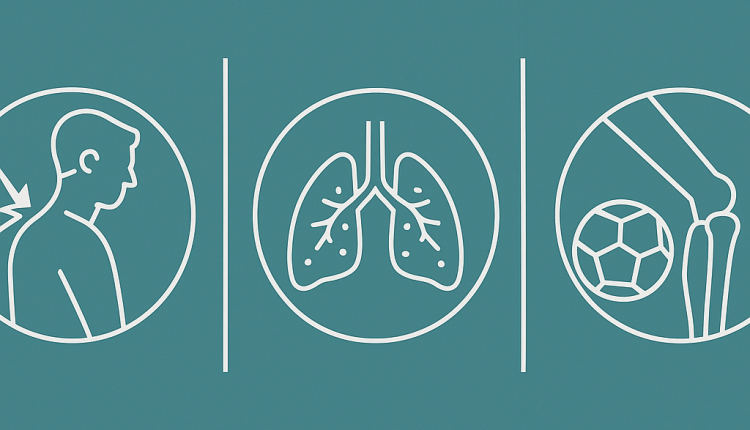

Yeni düzenleme kapsamında, aşağıdaki üç hastalık resmi olarak meslek hastalığı olarak tanımlandı:

- Omuz rotator manşetinde hasar: Uzun yıllara dayanan yoğun omuz yüklenmeleri sonucu oluşan yapısal hasar.

- Kronik obstrüktif bronşit ve amfizem: Uzun süreli kuvars tozu maruziyeti sonucu gelişen solunum sistemi hastalıkları.

- Gonartroz (diz kireçlenmesi): Profesyonel futbolcular arasında sık görülen, diz ekleminde oluşan aşınmaya bağlı hastalık.